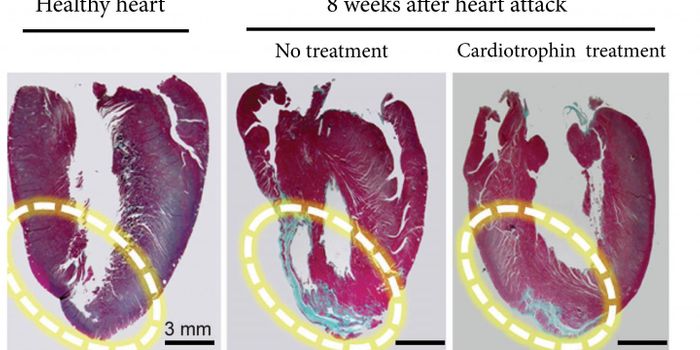

AUG 08, 2017

Cardiology

When the heart grows larger, it can be for one of two reasons. One reason is a result of heart failure, where heart cell

...

Written By:

Kara Marker